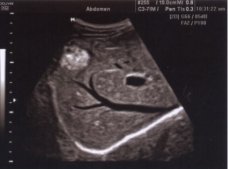

A ultrassonografia ou ecografia abdominal sem se utilizar de radiações ionizantes permite avaliar as estruturas abdominais, do ponto de vista dinâmico, morfológico e alterações texturais.

A ultrassonografia abdominal é realizada para avaliar:

. Fígado

. Pâncreas

. Baço

. Rins

. Vesícula e vias biliares

. Aorta abdominal e outros vasos abdominais.